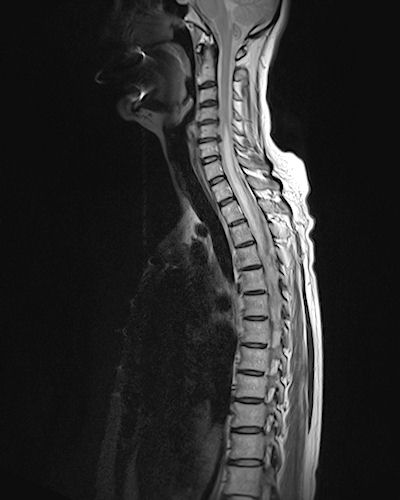

show the lesion, please

Mark the lesion in the scan